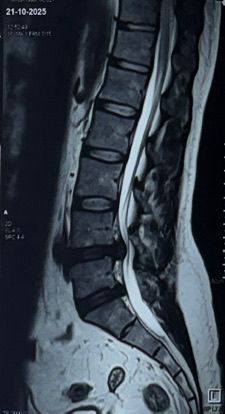

Diagnosis: As seen in the MRI below, he had a massive disc herniation compressing the nerve root. Conservative management (rest/meds) had failed.

Pre-Op MRI Scan showing herniated disc

Fig 1: Pre-Op MRI showing severe nerve compression.